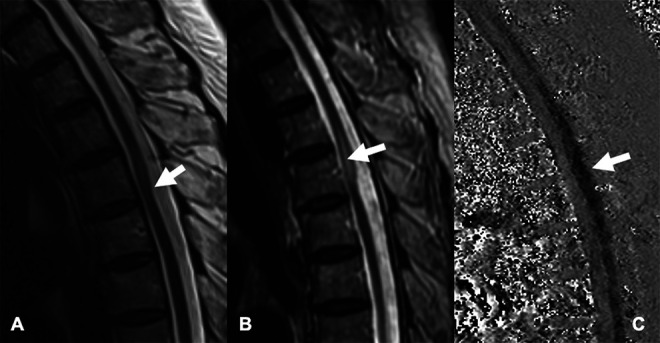

A 66-year-old woman without significant medical history other than hypertension presented with recent exacerbation of chronic back pain, progressive lower extremity weakness, gait ataxia, and mild fecal and urinary incontinence. Magnetic resonance imaging (MRI) showed ventral displacement and dorsal indentation of the thoracic spinal cord at T4–5, upstream edema at T3–4, and no evidence of syringomyelia (Fig. 1A). Cerebrospinal fluid (CSF) flow MRI (Fig. 1B) showed robust biphasic CSF flow posterior to the spinal cord at the site of compression, indicating the lack of a detectable obstructing lesion, such as an arachnoid cyst. Computed tomography (CT) myelography showed homogeneous intrathecal contrast opacification on early and delayed images (Fig. 2A), anterior cord displacement, and severe posterior cord flattening (Fig. 2B), which are suggestive of an arachnoid web.

FIG. 1.

MRI of the thoracic spine, sagittal views. A: T2-weighted imaging shows an indentation in the posterior aspect of the cord (arrow) consistent with the scalpel sign, which is highly suggestive of arachnoid web. B: Short-T1 inversion recovery imaging shows edema and focal cord enlargement cephalad to the indentation (arrow). C: Phase-contrast CSF imaging shows no detectable impediment to CSF flow posterior to the cord (arrow).

Current radiological diagnosis of arachnoid webs relies primarily on the scalpel sign on sagittal MRI or CT myelography. The sign consists of an indentation of the posterior spinal cord that resembles a surgical scapula with the blade pointing posteriorly (Figs. 1 and 2). Direct visualization of an arachnoid web on MRI has so far been reported only once.2 Although indirect evidence of CSF flow impairment may be obtained, that did not occur with our patient (Fig. 1). Other radiological signs include spinal cord edema and syrinx formation. Most reported cases were associated with syringomyelia, usually rostral but possibly caudal to the level of indentation.5 CSF flow impediment from posterior subarachnoid space obstruction, even if not demonstrated on CSF flow studies, as in our patient, may cause a pressure gradient (Venturi effect) from intramedullary passage of CSF through perivascular spaces during systole, resulting in cord edema (Figs. 1 and 2) that eventually culminates in syrinx formation.40 Other serious diagnostic considerations are spinal cord herniation and arachnoid cyst. In spinal cord herniation, a focal anterior spinal cord protrusion through a ventral dural defect41,42 may be difficult to identify on imaging. Arachnoid cysts have well-marginated walls, cause smooth scalloping on the spinal cord surface that is seen on MRI or CT myelography,43 and behave like space-occupying lesions on CSF flow studies.